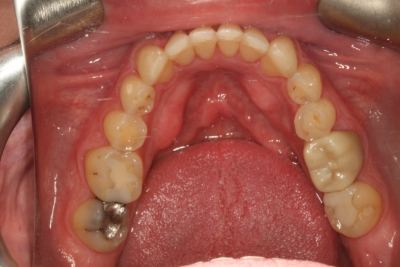

矯正治療後、私たちは間接修復のために上顎弓を準備し、ダレンに仮の修復物を装着しました。 また、下顎切歯縁をダイレクトコンポジットで修復し、露出した象牙質を封鎖し、診断用ワックスアップから製作した熱可塑性ステントを用いて切歯面を整えました。 ステントを使用して切縁にダイレクトコンポジットを装着することで、時間を節約し、切縁の位置をより正確にすることができました。 その後、ダレンは歯周病専門医に送られ、歯肉の構造を修正しました。

ダレンは、軟組織が完全に治癒するのを待つために、3ヶ月間プロビジョナルを装着したままにしました。 これにより、審美性、音声学、咬合、および機能を評価することもできました。

このケースでは、患者の機能包絡線と調和するように前方誘導を工夫しなければならなかったので、プロビジョナルは特に重要なものでした。 プロビジョナルレストレーションを装着した当初、ダレンは犬歯の位置と輪郭に「固定されている」と感じ続けていました。